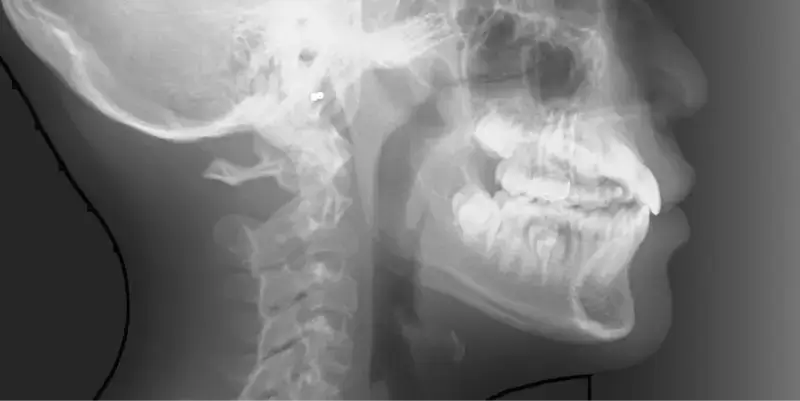

兒童早期矯正,又稱為「預防性矯正」或「第一階段矯正」,指的是在孩子乳牙或混合牙期(約7~10歲)時,就針對牙齒排列、咬合不正、牙弓發育等問題提前介入的矯正治療。 目的不只是「把牙齒排整齊」,更重要的是引導上下顎正常發育,減少未來拔牙、正顎手術的機率,讓恆牙有足夠空間健康萌發。

初步諮詢與X光評估

第1期:乳牙齒列期(6歲以前)

齒列混合期(7~10歲)

相當於國小低至中年級,這時會開始進到乳牙換成恆牙的階段,也是牙齒移動速度快的時期,在這個階段接受矯正能夠擁有良好的矯正效率,因此也被定義為「兒童矯正的黃金期」。

年齡第3期:恆牙期(11歲以上)

此時能觀察到孩童差不多已經換牙完成,雖然矯正效率可能沒有兒童矯正黃金期來的好,但是牙齒骨骼仍在持續生長,青少年的配合度相對更高,若開始接受矯正也能擁有良好的矯正成果。